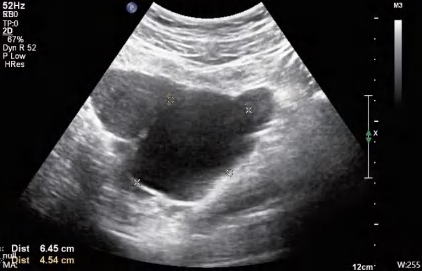

输卵管系膜囊肿扭转超声图